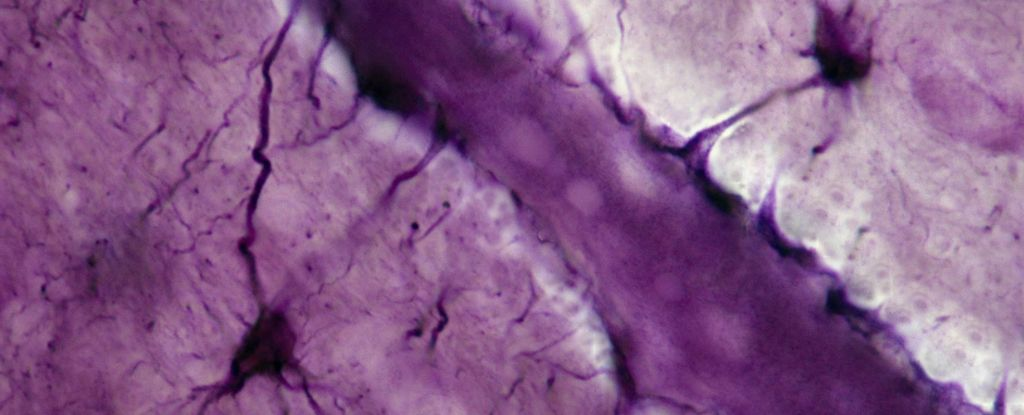

Більшість рецепторів CB1 у мозку впливають на нейрони, але деякі з цих тригерів також присутні в ненейрональних клітинах, званих астроцитами. Астроцити є найбільш поширеними клітинами в центральній нервовій системі, і останнім часом вони стали важливими регуляторами когнітивних функцій.

В “ногах” цих зіркоподібних клітин тискають на кровоносні судини в мозку, створюючи захисний бар’єр, через який можуть проходити тільки певні молекули. Згідно з новими експериментами на мишах, рецептори CB1 відіграють важливу роль у підтримці цілісності цього бар’єра крово-мозок.